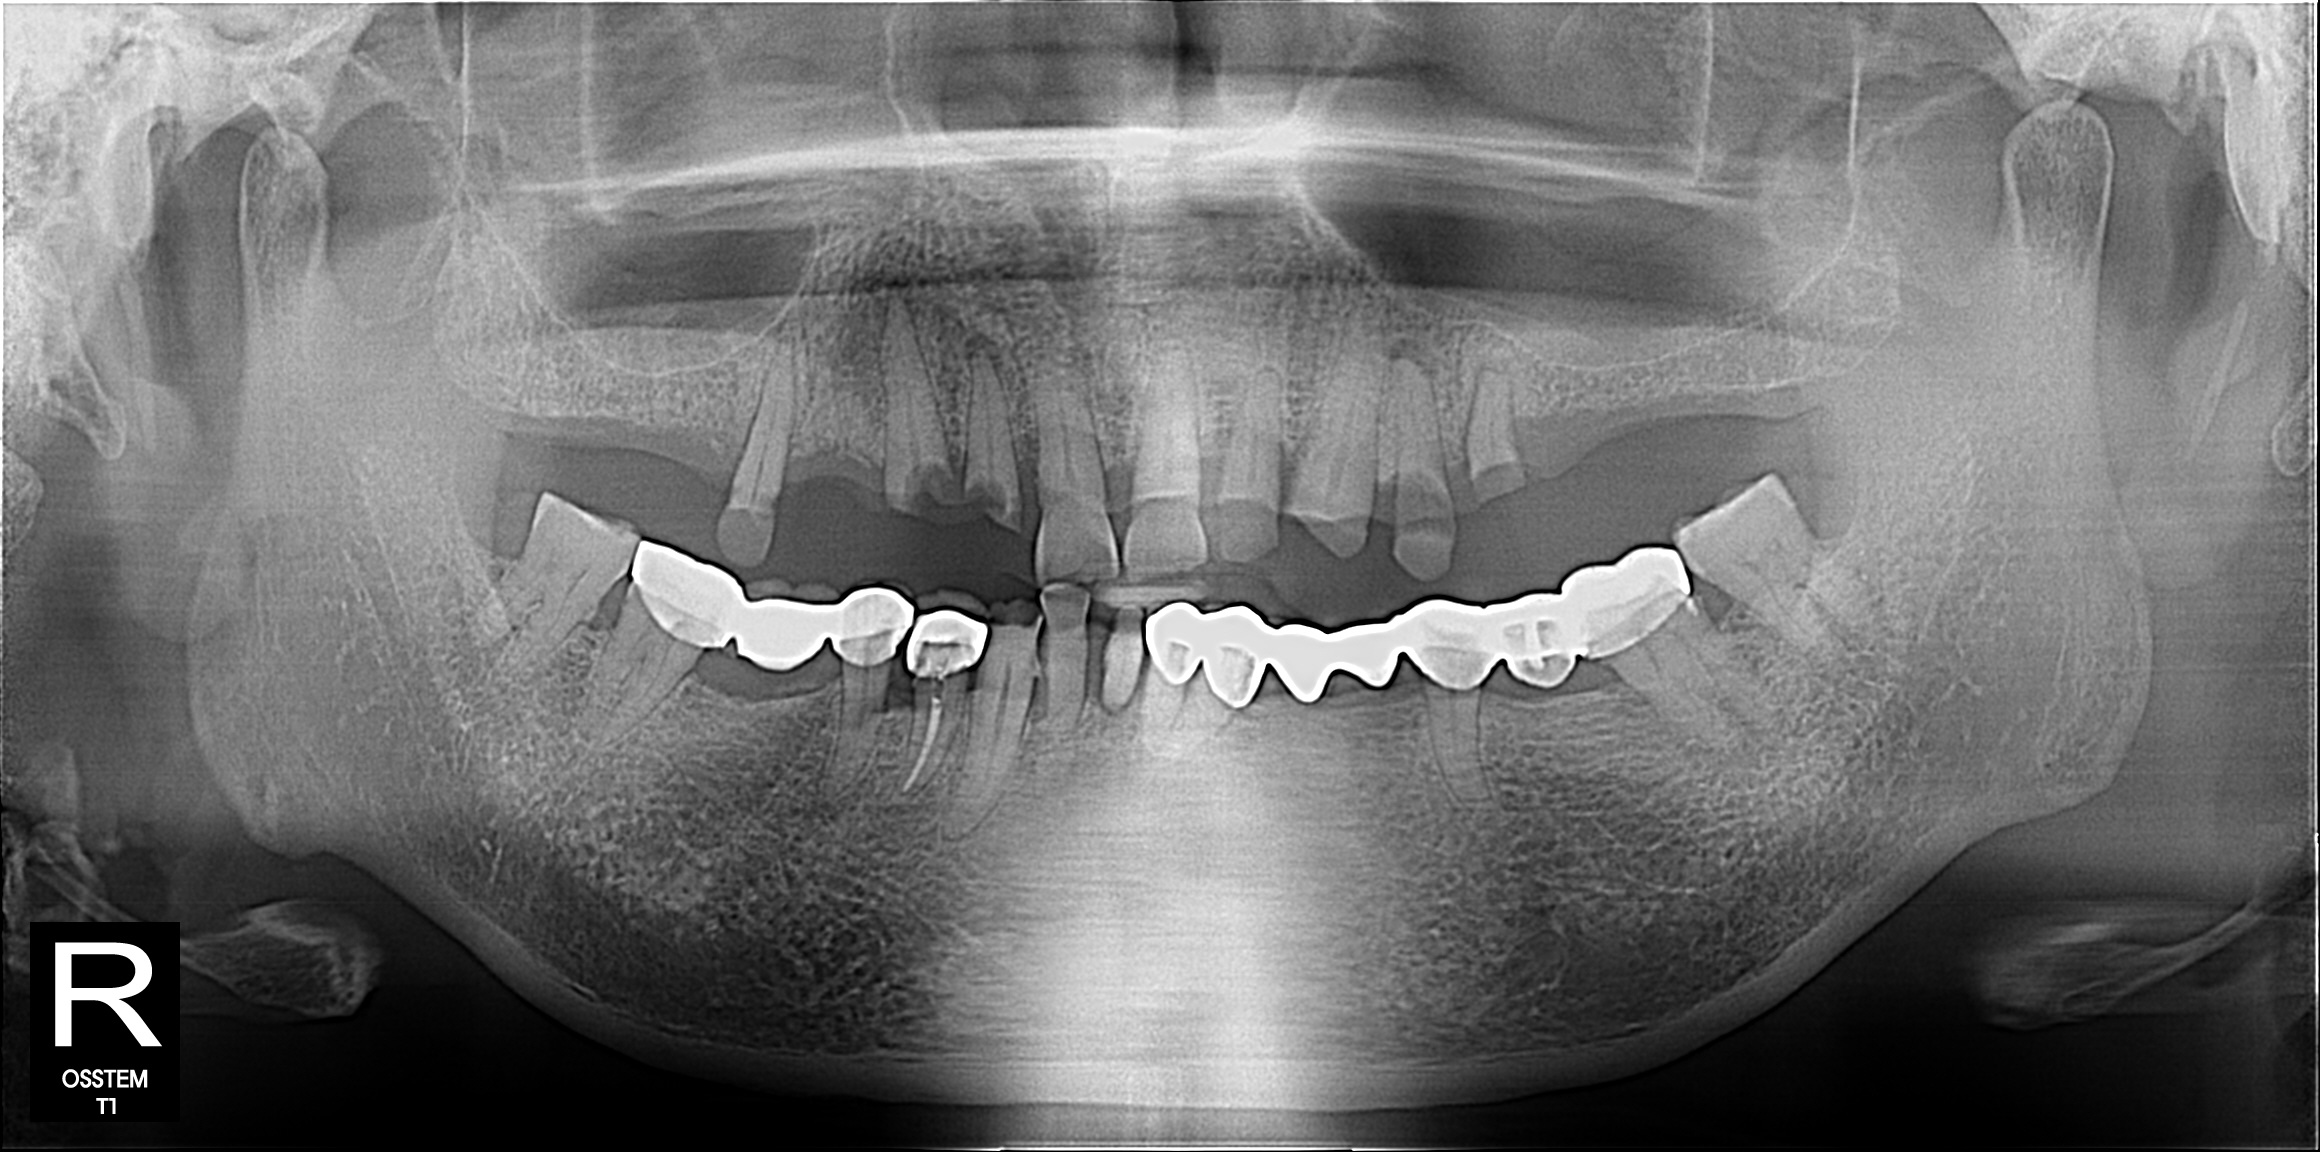

일반진료

BEFORE & AFTER